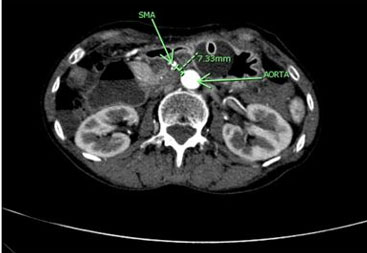

The patient presented intense epigastric pain, vomiting, and constipation, requiring hospitalization. Symptoms subsided when lowering enteral nutrition infusions up to 20 cc/h, and exacerbated when enteral nutrition volume was increased. The physical exam showed a normal abdomen, no distension, soft, with slight sensitivity at the epigastrium and no signs of peritoneal irritation. By this time, the patient’s weight was 36 kg, reaching a body mass index (BMI) of 16.8 kg/m2. An upper digestive endoscopy showed an esophageal stricture with actinic appearance, requiring endoscopic dilation. However, since stenosis does not explain the feeding intolerance, a CT scan was performed. It reported a significant decrease in intra-abdominal fat, especially in the retroperitoneal fat panniculus, associated with a change in caliber and dilation of the second and third portion of the duodenum (Figure 1 and Figure 2), possibly due to partial compression of the third portion between the aorta and the SMA. No other signs of intestinal obstruction were observed. Superior mesenteric artery syndrome was suspected so the images were reviewed with the radiologist, finding an aorto-mesenteric angle of 17° (Figure 3) and an aorto-mesenteric distance of 7.3 mm (Figure 4).

Figure 4: Reduced aorto-mesenteric distance in patient no. 1, transverse view.

Figure 6: Reduced aorto-mesenteric distance in patient no. 2, transverse view.